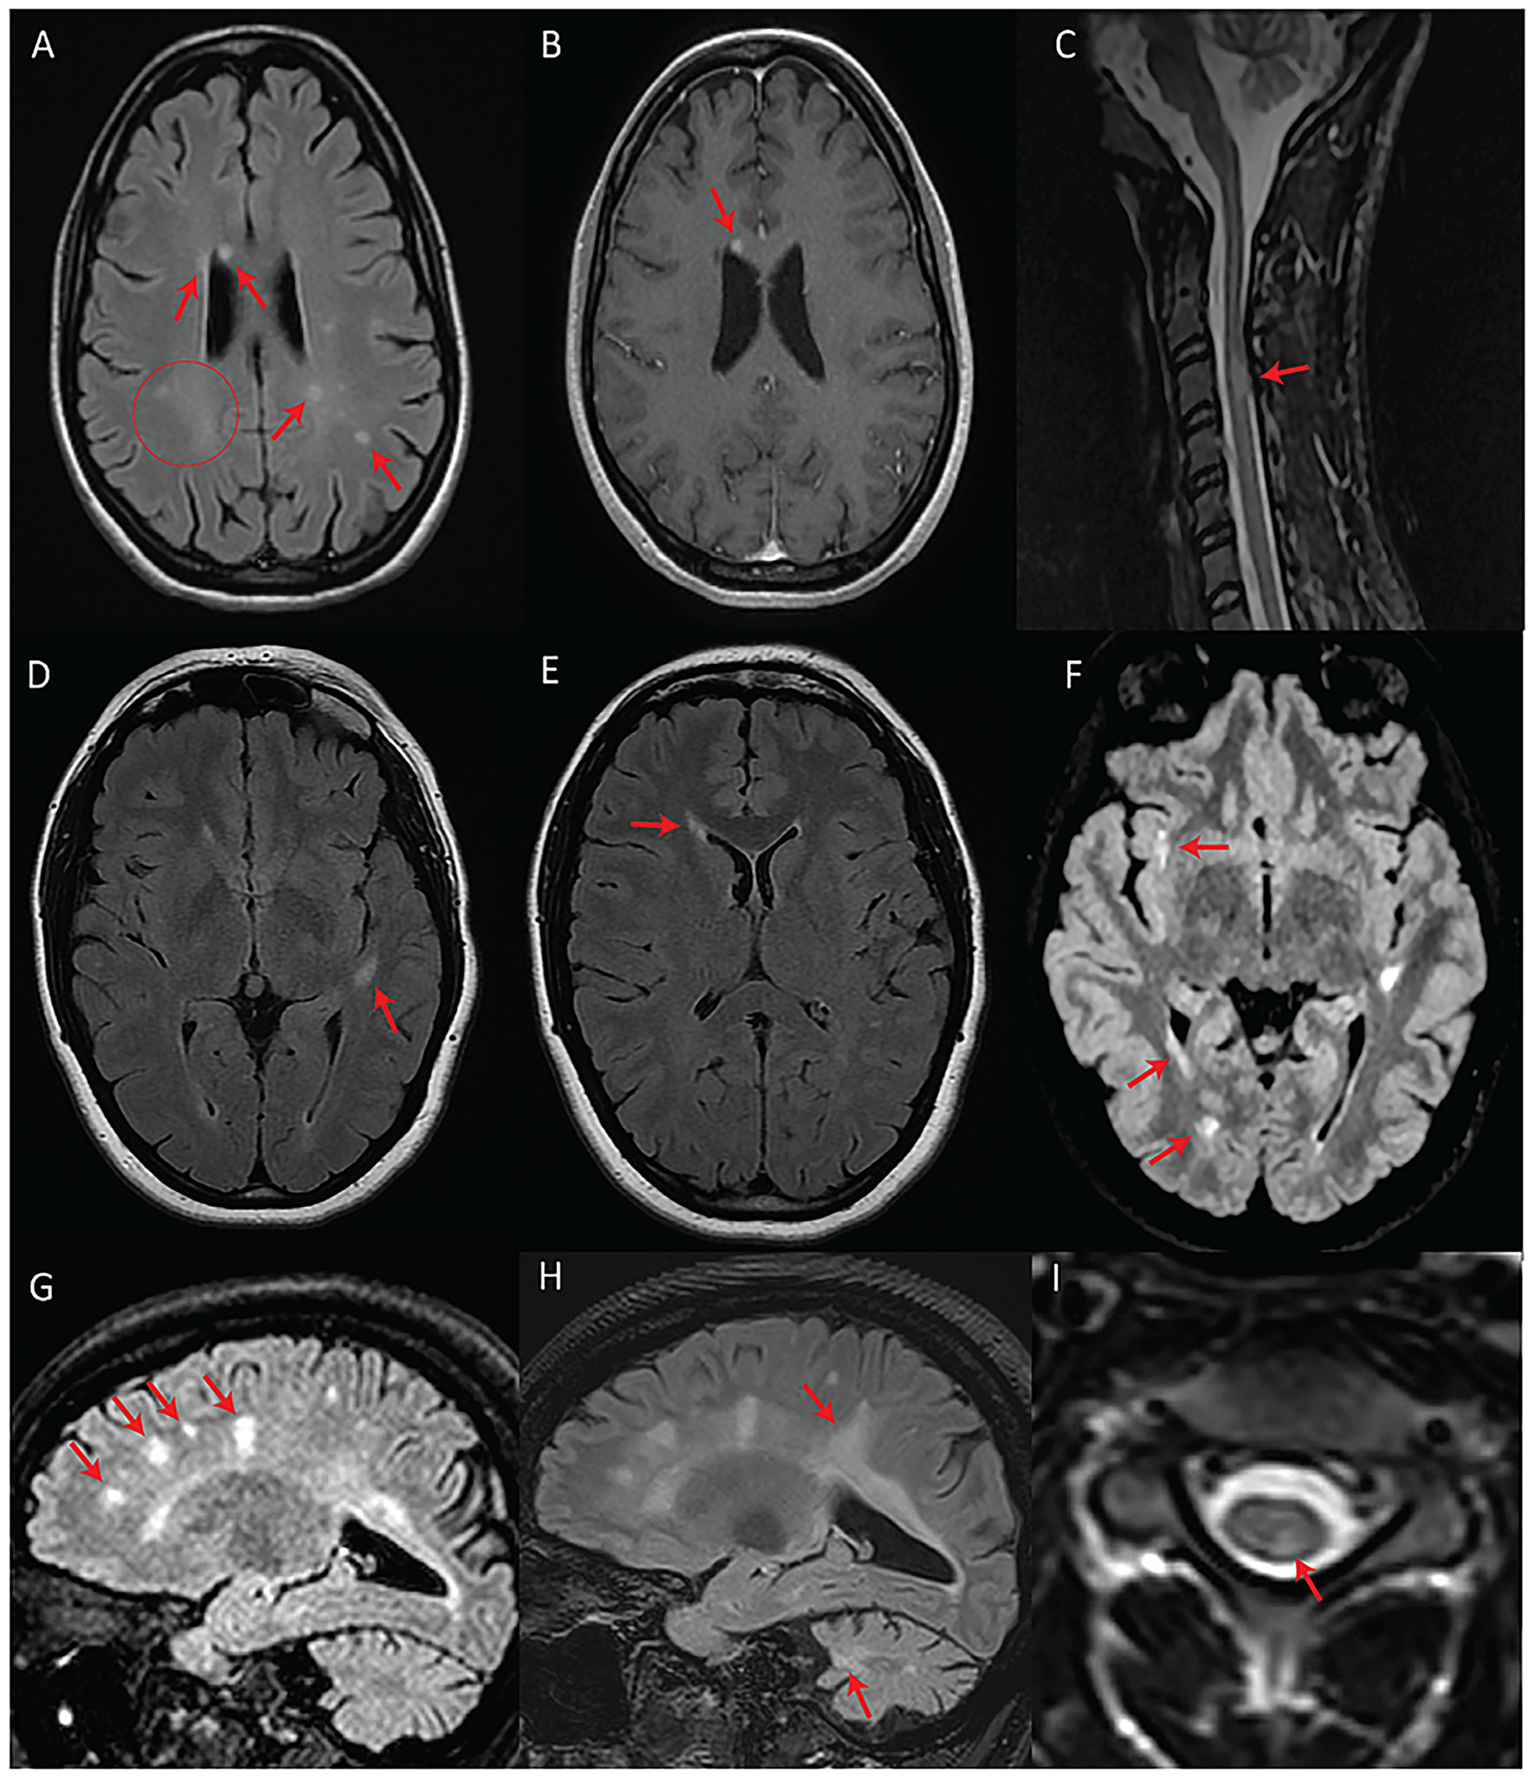

The mean age at the latest MRI available for review was 29 years old (range = 14–60 years). All subjects demonstrated at least one neuroradiological feature typical of WFS (Figure 1) (12–15). For 11 subjects (n = 11/17; 65%), two timepoints were available for assessment (mean follow-up MRI duration = 5.3 years).

Figure 1

Classical MRI features associated with WFS. (A) Axial T2-weighted image showing bilateral pontine signal abnormality (subject #10). (B) Axial T2-FLAIR image showing bilateral symmetric posterior white matter abnormal signal as well as a punctate, round white matter signal abnormality in the left frontal lobe (subject #14).

We detected T2-hyperintense white matter foci that were MS plaque-like (27–29) in seven subjects (n = 7/17; 41%) (Figures 2, 3). In four of these subjects (n = 4/17; 24%), the McDonald radiological criteria of dissemination in space and time were either fully (n = 3) or partially (n = 1) fulfilled, inciting consideration of a WFS-MS double diagnosis (Figure 2) (27). Some lesions in three of these four subjects showed gadolinium enhancement on T1-weighted imaging (Figure 2A), further supporting the existence of an underlying inflammatory process. Positive oligoclonal band status strongly supported a secondary diagnosis of MS (satisfaction of the full McDonald criteria, radiological and clinical) in the only two subjects for whom lumbar puncture was performed (#2 and #3). In both cases, a secondary diagnosis of MS was therefore communicated due to the presence of accompanying acute focal clinical deficits. MS treatment with teriflunomide was initiated in subject #3. Follow-up MRI after teriflunomide initiation documented stabilization of the multifocal white matter lesion load with worsening of pre-existing cerebellar atrophy and diffuse bilateral subcortical white matter involvement (Figures 2G–I). The observed locations and characteristics of MS-like focal lesions are summarized in Table 2.

Figure 2

Patients with fulfilled or partially fulfilled McDonald criteria. (A–C) Represent subject #2 (criteria fulfilled). (A) Axial T2-FLAIR image showing multifocal periventricular, callosal, and subcortical white matter lesions (arrows) with accompanying diffuse abnormal peritrigonal white matter signal (circle). (B) Post-gadolinium axial T1 image showing an enhancing callosal lesion. (C) Sagittal T2 image of the cervical and thoracic spinal cord showing a demyelinating lesion at the level of C3. (D–F) Represent subject #1 (criteria partially fulfilled). (D) Axial T2-FLAIR showing an oval-shaped lesion in the left temporal subcortical white matter. (E) Axial T2-FLAIR showing a periventricular lesion around the frontal horn of the right lateral ventricle. (F) Axial T2-FLAIR, performed 7 years after the first exam (D,E), showing new focal white matter lesions in the right insula, right periventricular white matter, and along the posterior horn of the right lateral ventricle. (G–I) Represent subject #3 (criteria fulfilled). (G) Sagittal T2-FLAIR showing multifocal white matter lesions perpendicular to the ventricular walls. (H) Sagittal T2-FLAIR, performed 4 years after initial MRI (G), demonstrating progression of the lesion burden in both the supra and infratentorial regions despite treatment with teriflunomide as of the first year in the 4-year interval. (I) Axial T2 spinal cord MRI showing a white matter lesion located in the left posterior cord at the C3 level.

In line with the hypothesis that some subjects in our study may be concomitantly suffering from WFS and MS, subject #3 responded to teriflunomide (Figures 2G–I). This was the only subject in our series who had started disease-modifying therapy for MS. While there is a possibility that the treatment had no impact on the natural course of WFS in this subject, it is plausible that underlying degenerative processes may have been exacerbated while inflammation was being suppressed. Even though the exact mechanisms contributing to this subject’s outcome remain undefined, simultaneous Wolframin/WFS1 deficiency and teriflunomide treatment might have imposed a significant mitochondrial stressor. Indeed, Wolframin/WFS1 plays an indirect, yet essential role in multiple facets of mitochondrial quality control putatively through modulation of Ca2+ homeostasis, while the mechanism of action of teriflunomide is the inhibition of dihydroorotate dehydrogenase, whose activity is intrinsically linked to the mitochondrial respiratory chain (19, 33). Thus, the classic WFS-associated neuroradiological features in this subject might have progressed, at least in part, because of a compounded mitochondrial insult, although dedicated studies are needed to validate this speculation.